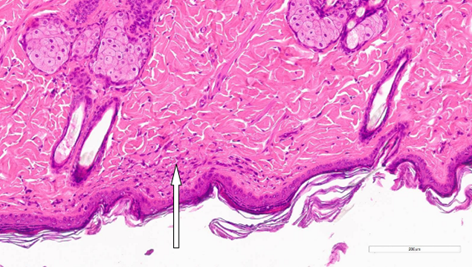

Морфологическое исследование образцов. Результаты микроскопического исследования биоматериала, полученного у экспериментальных животных на 14-й день, свидетельствовали о наличии более выраженных морфологических изменений в группе1. Помимо истончения эпидермиса у одной особи (№3), лазерное воздействие способствовало изменениям стратификации сетчатого слоя дермы (особь №2; рис.3) и коллагеновых волокон (особь №3). При этом изменения в дерме у животных из группы2 были выражены в меньшей степени, за исключением ангиоматоза у крысы №3, который сопровождался воспалительной реакцией в поверхностном слое дермы (рис. 4).

Рис. 3. Очаговое нарушение стратификации сетчатого слоя дермы на 14-й деньпосле процедуры воздействия CO2-лазером. Окрашивание гематоксилином и эозином (х200). Примечание: рисунок составлен авторами по результатам данного исследования